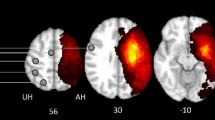

Alterations in connectivity were investigated between healthy controls and stroke patients 2 weeks post-stroke and local changes in connectivity between at 2 weeks and 3 months post-stroke (Fig. 1, Supplementary Tables 1, 2). Most altered connections were weakened 2 weeks post-stroke compared to healthy controls and strengthened for 3 months after the onset. Interhemispheric connections comprised mostly altered connections. In contrast, several intrahemispheric connections of the IFS and IFG were strengthened at 2 weeks post-stroke compared to healthy controls and weakened during the recovery period, the opposite pattern of other connections.

Differences in connectivity between healthy controls and stroke patients at 2 weeks post-stroke (a) and changes in connectivity between 2 weeks and 3 months post-stroke (b). This figure was drawn using BrainNet Viewer software (http://nitrc.org/projects/bnv/). The red edge represents an increase in the strength of the connection, and the blue edge represents a decrease in the strength of the connection (p < 0.05). IL ipsilesional side, CL contralesional side